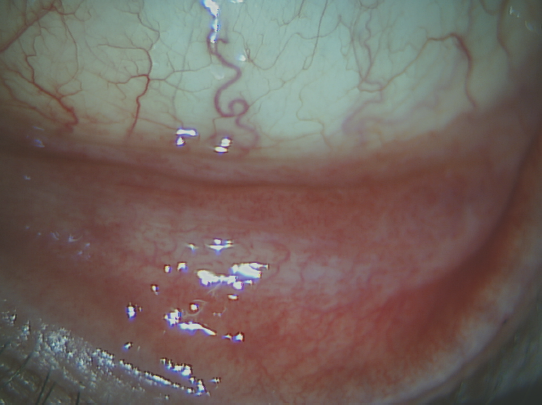

Через 3 месяца после курса психотерапии пациент был повторно осмотрен. Объективно оба глаза: конъюнктива бледно-розового цвета, фолликулов и отделяемого нет, белёсых атрофированных участков конъюнктивы нет, окрашивания бенгальским розовым нет (рис. 6), проба Норна — 10–12 с, LIPCOF-тест — степень 1 на OU.

Рис. 6. Состояние конъюнктивы нижнего века через 3 месяца

Fig. 6. Lower eyelid conjunctiva condition after 3 months